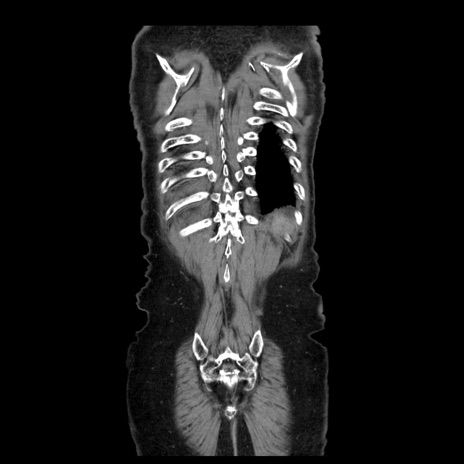

横断像

【症例】70歳代男性

【主訴】腹痛

【現病歴】肝硬変・肝細胞癌にてかかりつけの方。約9時間前に食後より腹痛出現。症状が徐々に増悪し、嘔吐出現したため来院。

【既往歴】肝硬変、肝細胞癌(RFA、TACE後)

【身体所見】意識清明、表情苦悶様、BT 36℃、BP 129/78mmHg、P 88bpm、SpO2 97%(RA)、右上腹部から心窩部にかけて圧痛あり、反跳痛なし、筋性防御あり。

【データ】WBC 5800、CRP 0.16